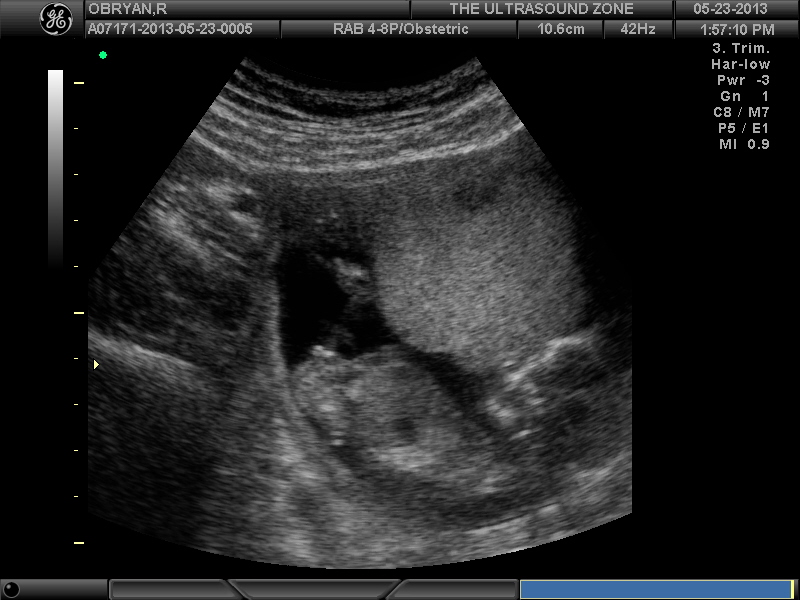

Here is my 13 week U/S and my 15 week U/S both elective. I will have my 20 week scan in the doc offince on July 3rd.

The reason I am not convinced girl is the first scan is was said leaning girl then doc said leaning boy then last scan said girl. I do not think I will be 100% convinced until my 20 weeek U/S.